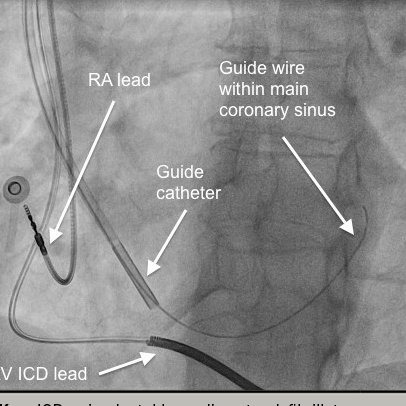

سلك توجيه او السلك المرشد (Guide wire)

فائدة القايد واير هي انه يساعدنا بعد ادخال الابرة في الوعاء الدموي بالتأكد من اننا في الاتجاه الصحيح داخل الوعاء الدموي ونستطيع ان نراه بجهاز الفلورو، ويساعدنا في الوصول الى منطقة الليجون او المنطقة المرادة في الوعاء الدموي ويعتبر كدليل او مرشد للكاثيتر للوصول للمنطقة المرادة.

الكاثيتر تأتي بعدة اشكال وقياسات ومهام على حسب شكل الوعاء الدموي،كل منطقة في الاوعية الدموية لها كاثيتر مناسبة لها.

نستفيد منها اننا إذا وصلنا للمنطقة المرادة نحقن الصبغة ونشخص المشكلة لدى المريض.

بعض أنواع الكاثيتر نوصل من خلالها البالونات والدعامات والطرق العلاجية الاخرى.